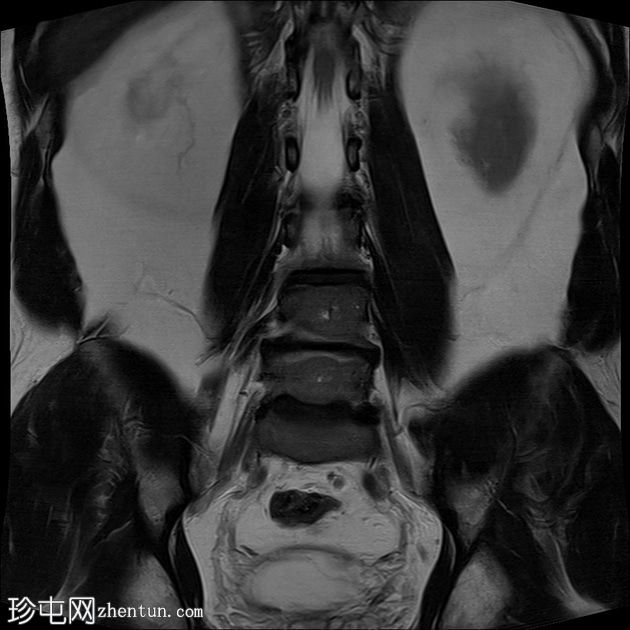

冠状面

T2

T1加权和T2加权序列中L4和L5椎体终板信号强度增加,STIR图像中信号丢失,符合Modic 2型退行

性病

变。L4-5椎间盘退行性病变。

这些发现符合Modic 2型病变,反映了慢性退行性疾病继发的骨髓脂肪替代。此类病变通常与长期机械应力有关。